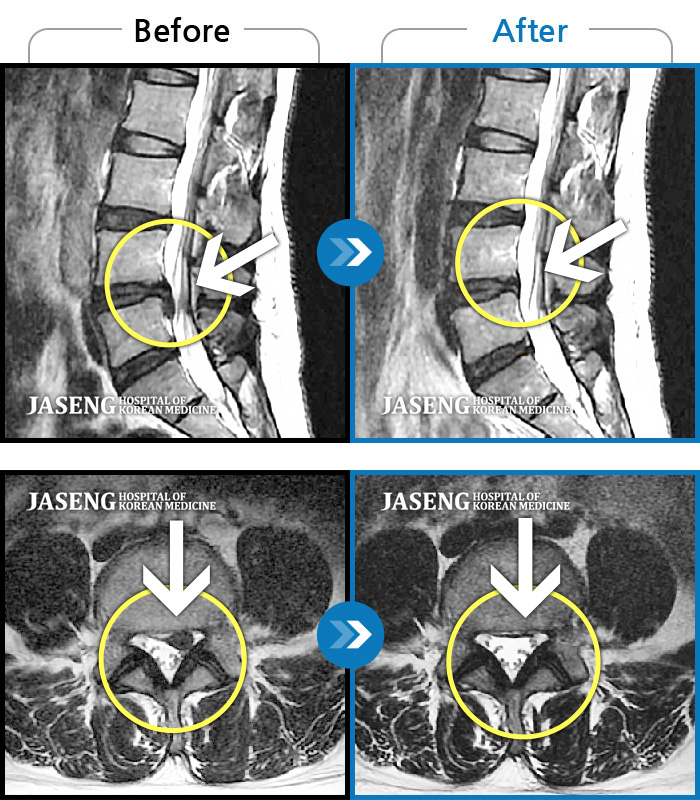

MRI 치료사례

좌측 엉덩이부터 종아리까지 저림 및 통증